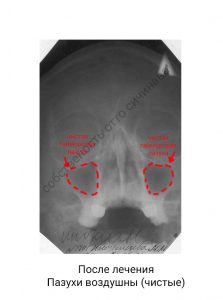

Таким образом, при неосложненных синуситах (гайморит, фронтит) достаточно около восьми комфортных, бескровных процедур для излечения. Процедура настолько безболезненна, что из проводят с четрехлетнего возраста.

Именно благодаря дренажному спрею, мы смогли вылечить несколько тысяч москвичей, с направлениями в больницу для проколов и хирургического вмешательства.